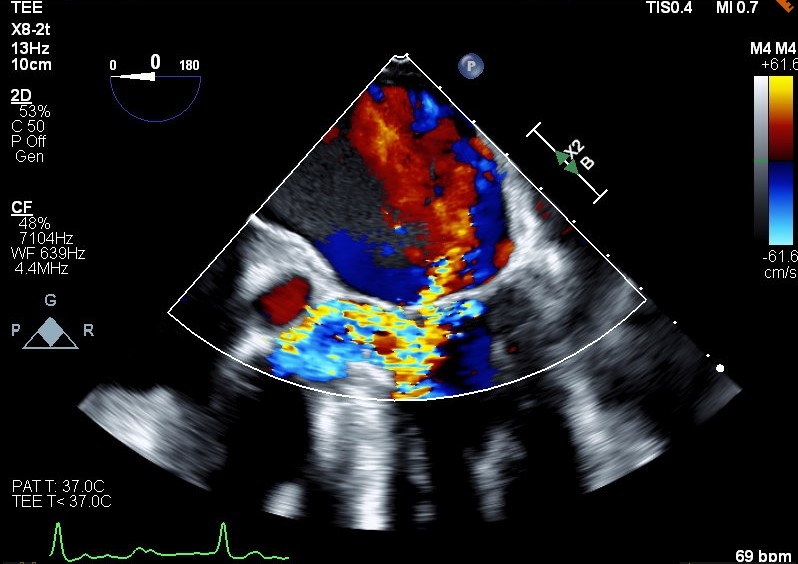

This case demonstrates classic cardiac physiology revealed in an unorthodox manner. Our patient is a 76-year-old male with a past medical history of HOCM, CAD, mild mitral regurgitation who presents to the hospital in the setting of chest pain. Work up revealed a high sensitivity troponin trend concerning for NSTEMI. Patient underwent a left heart cath where he was found to have a proximal LAD lesion with 99% stenosis requiring stenting. Post-intervention patient developed recurrent chest pain and a stat echocardiogram raised concerns for impending cardiogenic shock. Patient thus underwent emergent left and right heart cath. Impella LVAD placed for hemodynamic support. TEE was later obtained revealing moderate to severe mitral regurgitation, representing a progression from prior. At this time both advanced heart failure and structural heart service were consulted. The progression of the patient’s mitral regurgitation was thought to be impacting clinical deterioration and mitral valve transcatheter edge-to-edge repair (TEER) was discussed to address MR in the setting of obstruction. A multidisciplinary meeting resulted in decision to proceed with mitral valve TEER. Baseline hemodynamic gradients confirmed the presence of HOCM with peak-to-peak pressure gradient of 110 mmHg. Intraoperative TEE confirmed the presence of SAM and severe MR. The patient was prepared for a Pascal ACE clip, though in setting of this procedure phenylephrine was required for blood pressure support, revealing improvement in both SAM and MR. The patient was hemodynamically challenged with phenylephrine resulting in temporary resolution of MR and LVOT obstruction. These findings demonstrated a competent mitral valve with regurgitation resulting from HOCM physiology. After a multidisciplinary discussion, decision made to abort and withhold MV TEER.

This case demonstrates classic HOCM physiology in the setting of an attempted TEER procedure. With the addition of phenylephrine and increased afterload SAM resolved, as did much of the patient’s valvular regurgitation. This confirmed a competent mitral valve impacted by HOCM physiology rather than primary mitral valvular pathology. This case demonstrates the impact of structural imaging and competent imagers in the setting of complex anatomy and physiology. In this case TEE findings from provocative hemodynamic testing prevented unnecessary procedures.